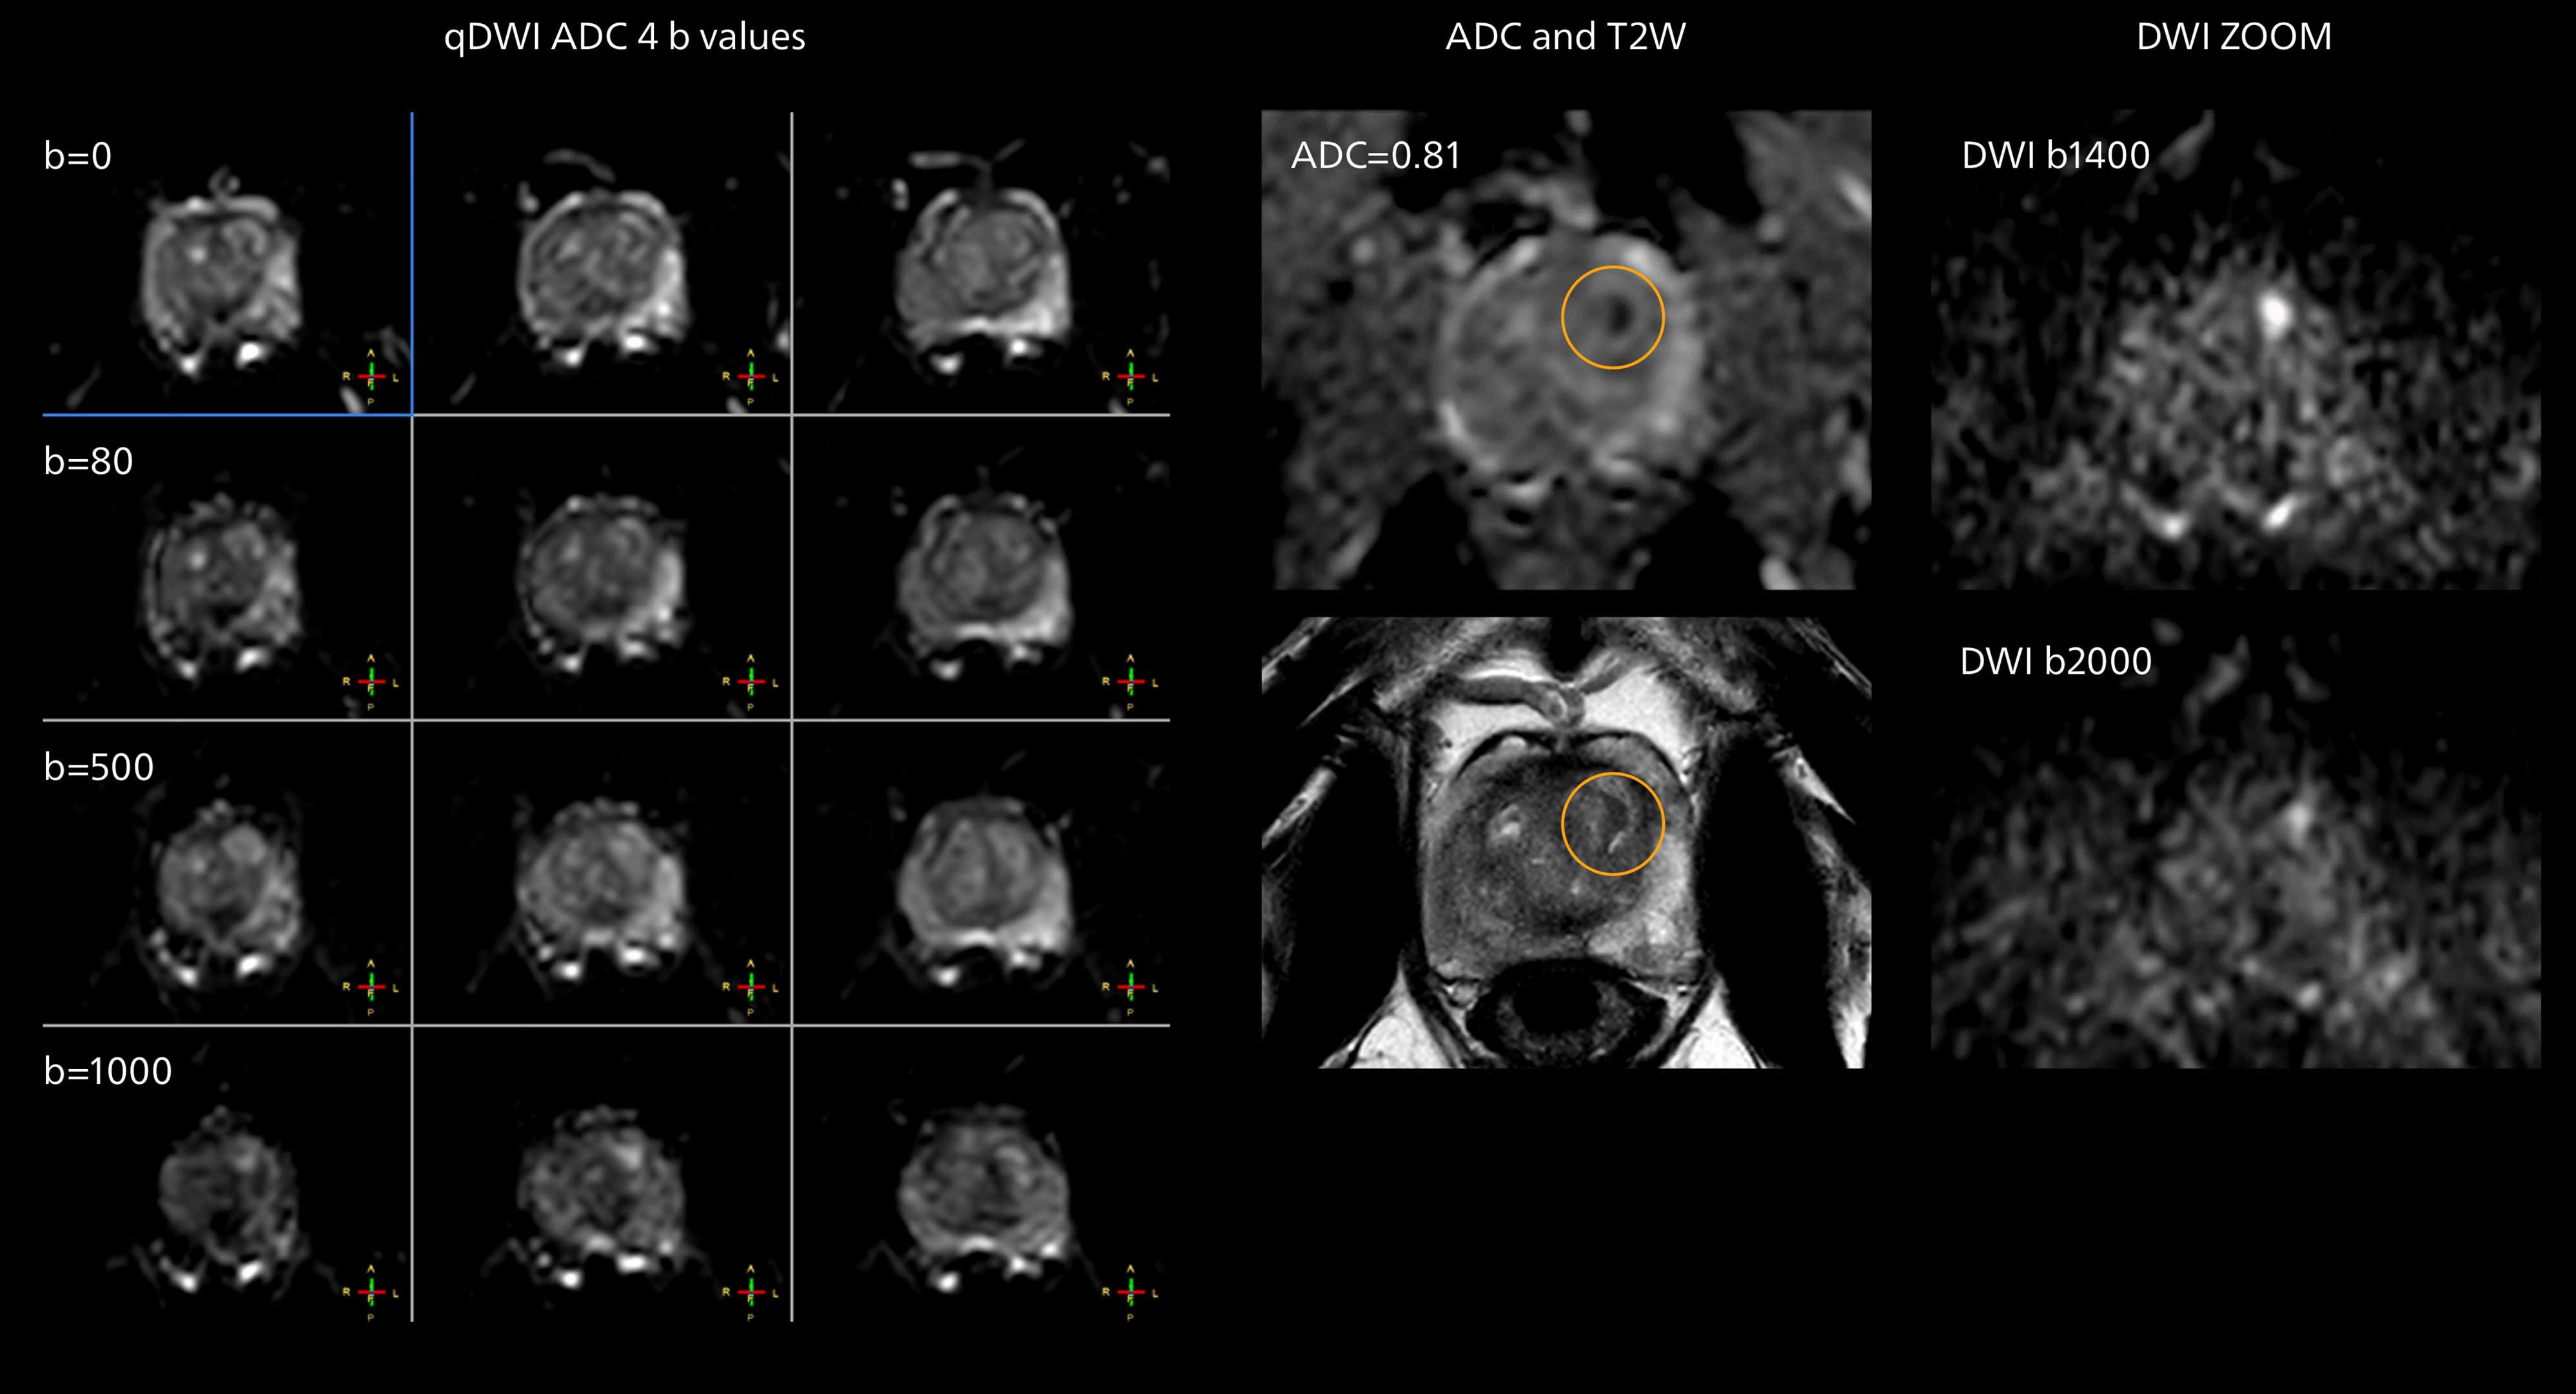

The examples on the left show the regular clinical diffusion protocol with four b-values up to b1000 s/mm². On the right, the T2W image shows a hypointense lesion that has low ADC and is clearly visible in b1400 and b2000 diffusion images, suggesting malignancy.

“From our experience, the diffusion imaging (DWI) seems to provide the most useful information in this process. And it is exactly the diffusion imaging that benefits much from the powerful MR 7700 gradients. So, we will investigate how even higher resolution DWI may enable an innovative approach in this area. The team also aims to investigate multiparametric imaging in combination with machine learning.”

The prostate DWI done so far with the MR 7700 looks promising; the quality of visualizing the gland and the areas of disease seems significantly improved. “In one of our first prostate patients we were already able to acquire a quite high-resolution diffusion image – using a b-value of 3000 – that clearly delineated the prostate lesion. That was a very nice example of what the MR 7700 gradients can achieve,” he says.

In one of our first patients we were able to acquire a quite high resolution diffusion image with a b-value of 3000, which clearly delineated the prostate lesion.”